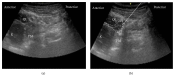

Purpose of Review. Since the original publication on the quadratus lumborum (QL) block, the technique has evolved significantly during the last decade. This review highlights recent advances in various approaches for administering the QL block and proposes directions for future research. Recent Findings. The QL block findings continue to become clearer. We now understand that the QL block has several approach methods (anterior, lateral, posterior, and intramuscular) and the spread of local anesthetic varies with each approach. In particular, dye injected using the anterior QL block approach spread to the L1, L2, and L3 nerve roots and within psoas major and QL muscles. Summary. The QL block is an effective analgesic tool for abdominal surgery. However, the best approach is yet to be determined. Therefore, the anesthetic spread of the several QL blocks must be made clear.